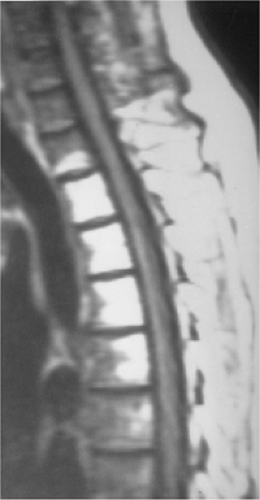

93e41b2c0cd00b407e9dbe829c33eb23.png

图-7戈谢病。MR显示双膝和脊柱骨髓内呈T1低信号。